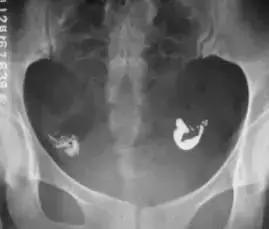

宫腔粘连

慢性输卵管炎